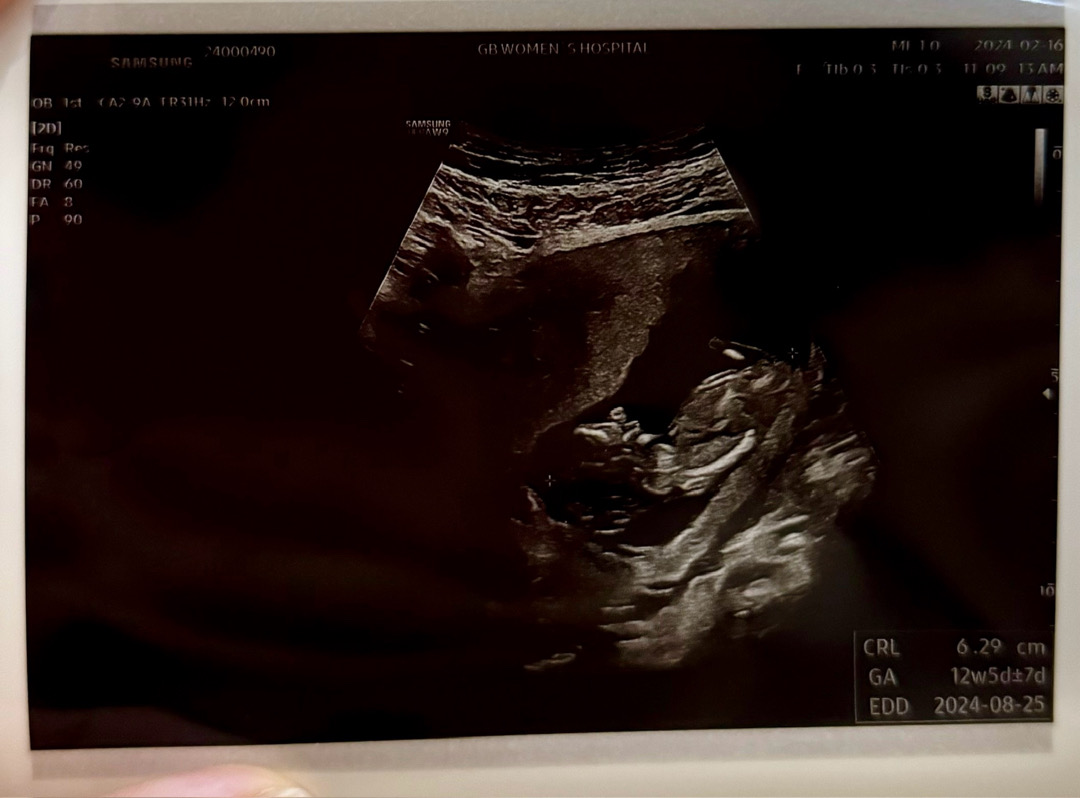

12주 1일차 각도법 문의합니당!!!

입체초음파만 계속 쳐다보다가 아!싶어서 혹시!하는 맘에 올려봅니당ㅋㅋㅋ 각도법 알아보는 분들 댓글 살포시 남겨주실 수 있으실까요? >_<*